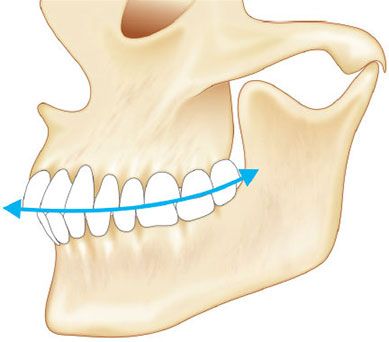

2. Неправильный прикус. Одна из самых распространённых причин развития асимметрии лица и челюсти. Асимметрия при этом возникает, потому что препятствия, создаваемые зубами, и аномалии прикуса могут вызывать смещение нижней челюсти в неправильное положение при полном окклюзионном контакте (при смыкании челюстей) [3].

- Перекрёстный прикус — смещение зубов или нижней челюсти вправо или влево. Это одна из наиболее частых причин развития асимметрии челюстей и лица. Происходит смещение ВНЧС, изменяются движения головки мыщелкового отростка, появляются щелчки и боли в ВНЧС, увеличиваются жевательные мышцы и развиваются головные боли. Приобретённые причины перекрёстного прикуса:

Виды неправильного прикуса

Если асимметрию вызывает неправильный прикус, то также нарушается работа ВНЧС и жевательных мышц, стираются зубы и изменяются пропорции лица. Это происходит из-за неодинакового распределения жевательных сил при глотании и жевании на верхнюю и нижнюю челюсть, височные кости и основание черепа. Сначала с той стороны, где окклюзионная плоскость опускается, возникает бóльшее давление. Затем жевательная мышца на противоположной стороне постепенно теряет силу из-за хронического гипертонуса (перенапряжения). У человека снижается амплитуда движений челюсти и может развиться её асимметрия и деформация черепа [1].

Окклюзионная плоскость (воображаемая линия, на которой встречаются верхние и нижние зубы)